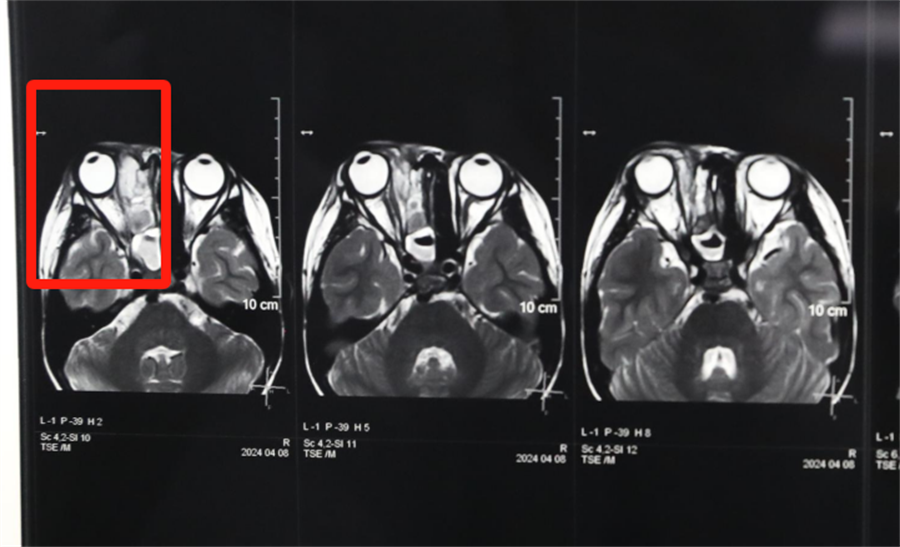

经眼科、耳鼻喉科联合会诊,医生发现孩子是因为患了急性鼻窦炎,导致右眼急性细菌感染,确诊为“右侧眶蜂窝织炎、眶内脓肿”。考虑到此病进展较快,可能导致视力下降甚至失明,耳鼻喉科立即将患儿收治入院。静脉输液、对症支持治疗、密切监测视力变化,一切有条不紊。入院第2天,孩子自觉右眼视力下降明显,眼科紧急会诊发现,其右眼视力从患病前的1.0下降到0.4。

北京儿童医院常驻专家、啪啪网 副院长杨小健决定立即手术治疗引流眶内脓液,并组织多学科联合会诊。考虑到患儿年龄较小,杨小健副院长决定采取内镜经鼻腔手术引流脓液,这种手术方式创伤小、恢复快、效果确切,而且避免了外切口瘢痕,不需要反复进行局部消毒换药。但是孩子鼻腔解剖结构本身就狭窄,而且处于急性感染期,术中出血风险较大,手术难度较高,对麻醉技术也有着很高的要求。

孩子左侧鼻腔3年来没有通气,鼻腔的发育受到了严重影响,甚至部分结构出现了一定程度的萎缩,并患有严重的鼻窦炎。杨小健副院长认真分析了孩子的病情,认为应该尽快手术治疗。